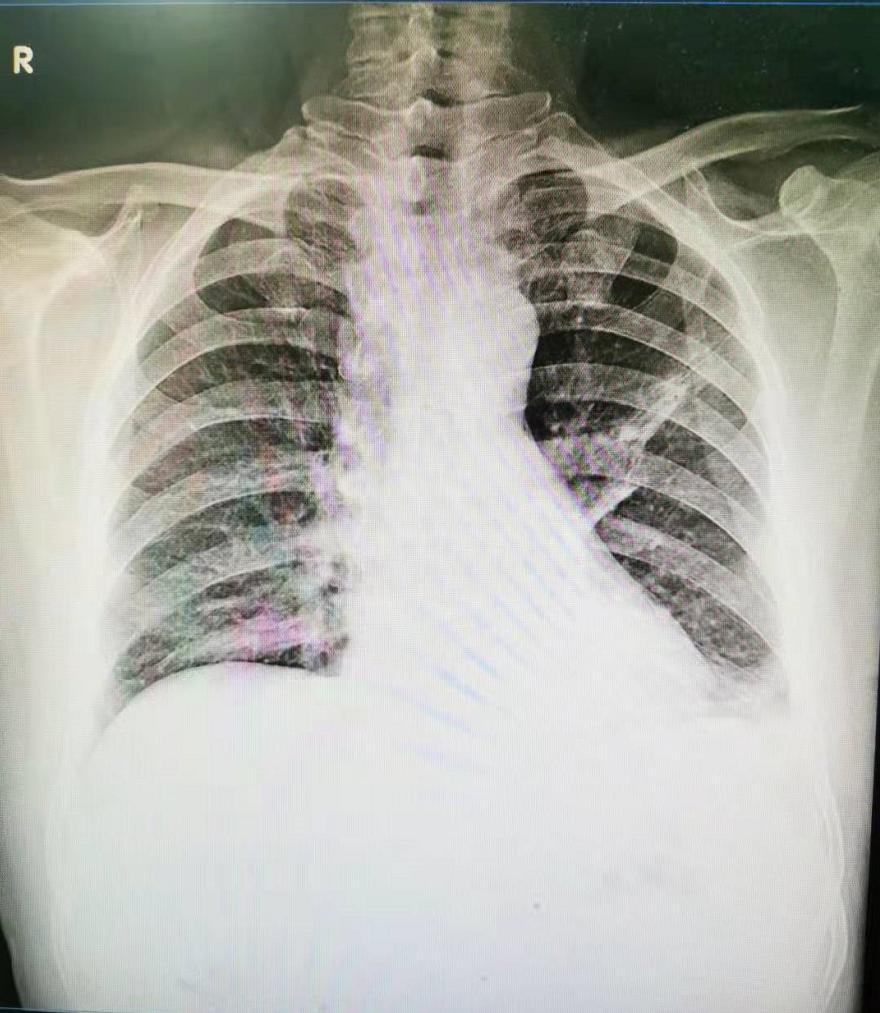

于是完善了胸片检查,结果显示:左肺中野条片状高密度影,左肋膈角变钝(图2)。

图2:左肺中野条片状高密度影,左肋膈角变钝。